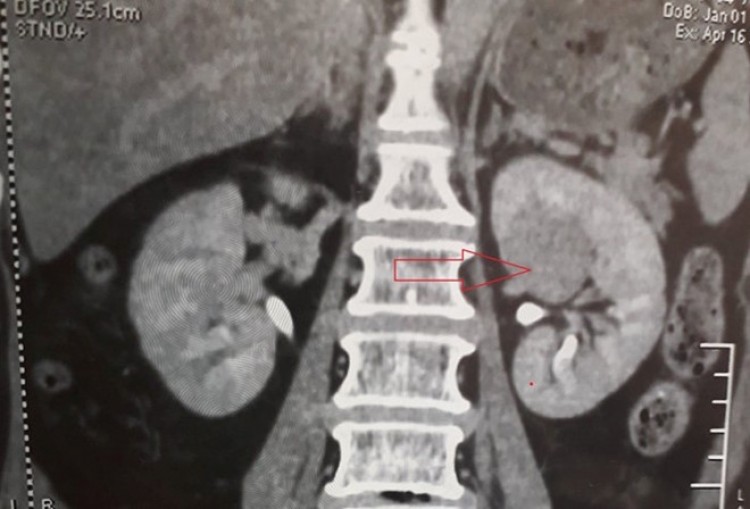

Khối u 28 mm nằm ngay trung tâm bể thận phải bệnh nhân ẢNH: ĐÌNH TUYỂN

Sau khi kiểm tra, các bác sĩ phát hiện bệnh nhân bị khối u 28 mm thận (T), do khối u ngay vị trí trung tâm của bể thận nên các bác sĩ hội chẩn quyết định cắt thận toàn phần để tránh trường hợp khối u có thể di căn trong thời gian tới.